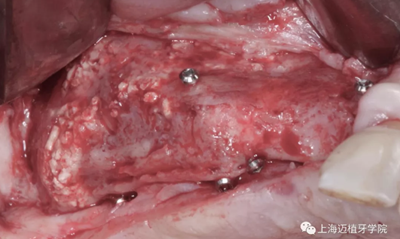

用骨釘固定骨板

GBR骨生物材料植骨失敗后,利用BBA植骨法及軟組織處理病例

四個月后成骨